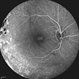

- Xlinked juvenile retinoschisis

- foveal schisis, spokewheel pattern

- Fundus photograph of a 27-year-old male with x-linked juvenile retinoschisis shows foveal retinoshisis with spokewheel pattern in his left eye.